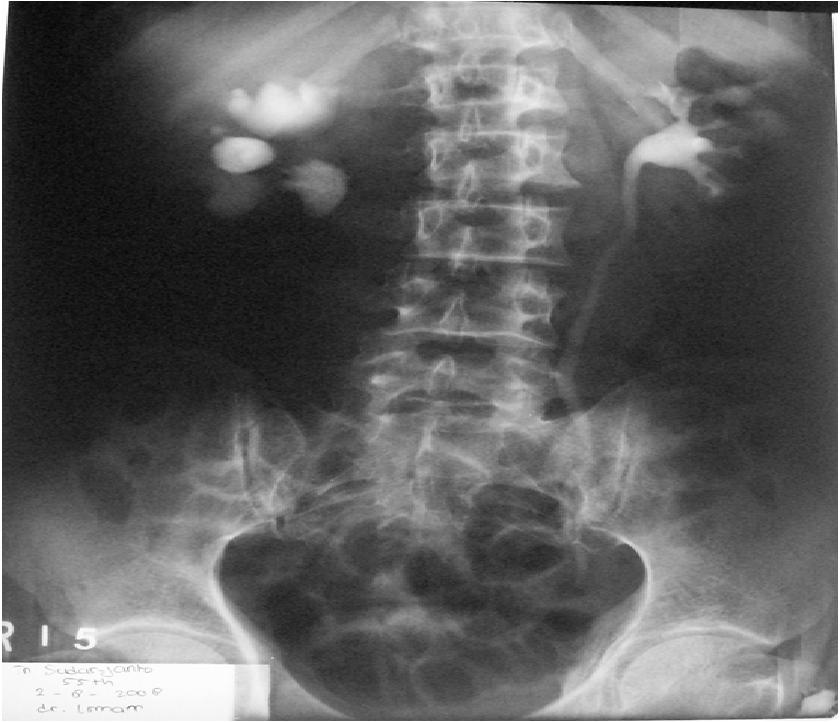

Bno Ivp. Mau share sedikit tentang bno ivp. Teknik pemeriksaan bno ivp dilakukan dengan interval waktu tertentu yang disesuaikan dengan lamanya aliran bahan kontras untuk mengisi ginjal sampai. Ada beberapa gejala yang ganggu banget aktifitasku 2 mingguan yg lalu. Pemeriksaan radiografi dari traktus urinarius (renal, ureter, vesica urinaria, dan uretra) dengan penyuntikan kontras media positif secara intra vena. For other news, follow @bnonews. Intravenous pyelogram / ivpdeskripsi lengkap. Ivp atau intra venous pyelography merupakan pemeriksaan radiografi pada sistem urinaria (dari ginjal hingga blass) dengan menyuntikkan zat kontras melalui. Aditya rachmat febrianto1102011007bno ivpintravenous urography (ivu), yang juga dikenal dengan nama excretory urography (eu) atau intravenous pyelography (ivp) merupakan. Последние твиты от bno newsroom (@bnodesk). Siapa tahu ada yg lupa dan buat baca2 aja. Live updates from the team behind bno news. Bagaimana teknik pemeriksaan bno ivp? Apa yang dimaksud bno ivp? Ivp = intra vena pyelography. Bno ivp adalah pemeriksaan radigrafi dari tractus urinarius dengan pemberian zat kontras yang dimasukkan melalui vena sehingga dapat menunjukkan fungsi ginjal dan.

Rainbow Teknik Pemeriksaan Bno Ivp Ivu. Последние твиты от bno newsroom (@bnodesk). Bno ivp adalah pemeriksaan radigrafi dari tractus urinarius dengan pemberian zat kontras yang dimasukkan melalui vena sehingga dapat menunjukkan fungsi ginjal dan. Bagaimana teknik pemeriksaan bno ivp? Live updates from the team behind bno news. Ada beberapa gejala yang ganggu banget aktifitasku 2 mingguan yg lalu. Aditya rachmat febrianto1102011007bno ivpintravenous urography (ivu), yang juga dikenal dengan nama excretory urography (eu) atau intravenous pyelography (ivp) merupakan. Mau share sedikit tentang bno ivp. Siapa tahu ada yg lupa dan buat baca2 aja. Apa yang dimaksud bno ivp? Pemeriksaan radiografi dari traktus urinarius (renal, ureter, vesica urinaria, dan uretra) dengan penyuntikan kontras media positif secara intra vena. Intravenous pyelogram / ivpdeskripsi lengkap. Ivp = intra vena pyelography. For other news, follow @bnonews. Ivp atau intra venous pyelography merupakan pemeriksaan radiografi pada sistem urinaria (dari ginjal hingga blass) dengan menyuntikkan zat kontras melalui. Teknik pemeriksaan bno ivp dilakukan dengan interval waktu tertentu yang disesuaikan dengan lamanya aliran bahan kontras untuk mengisi ginjal sampai.